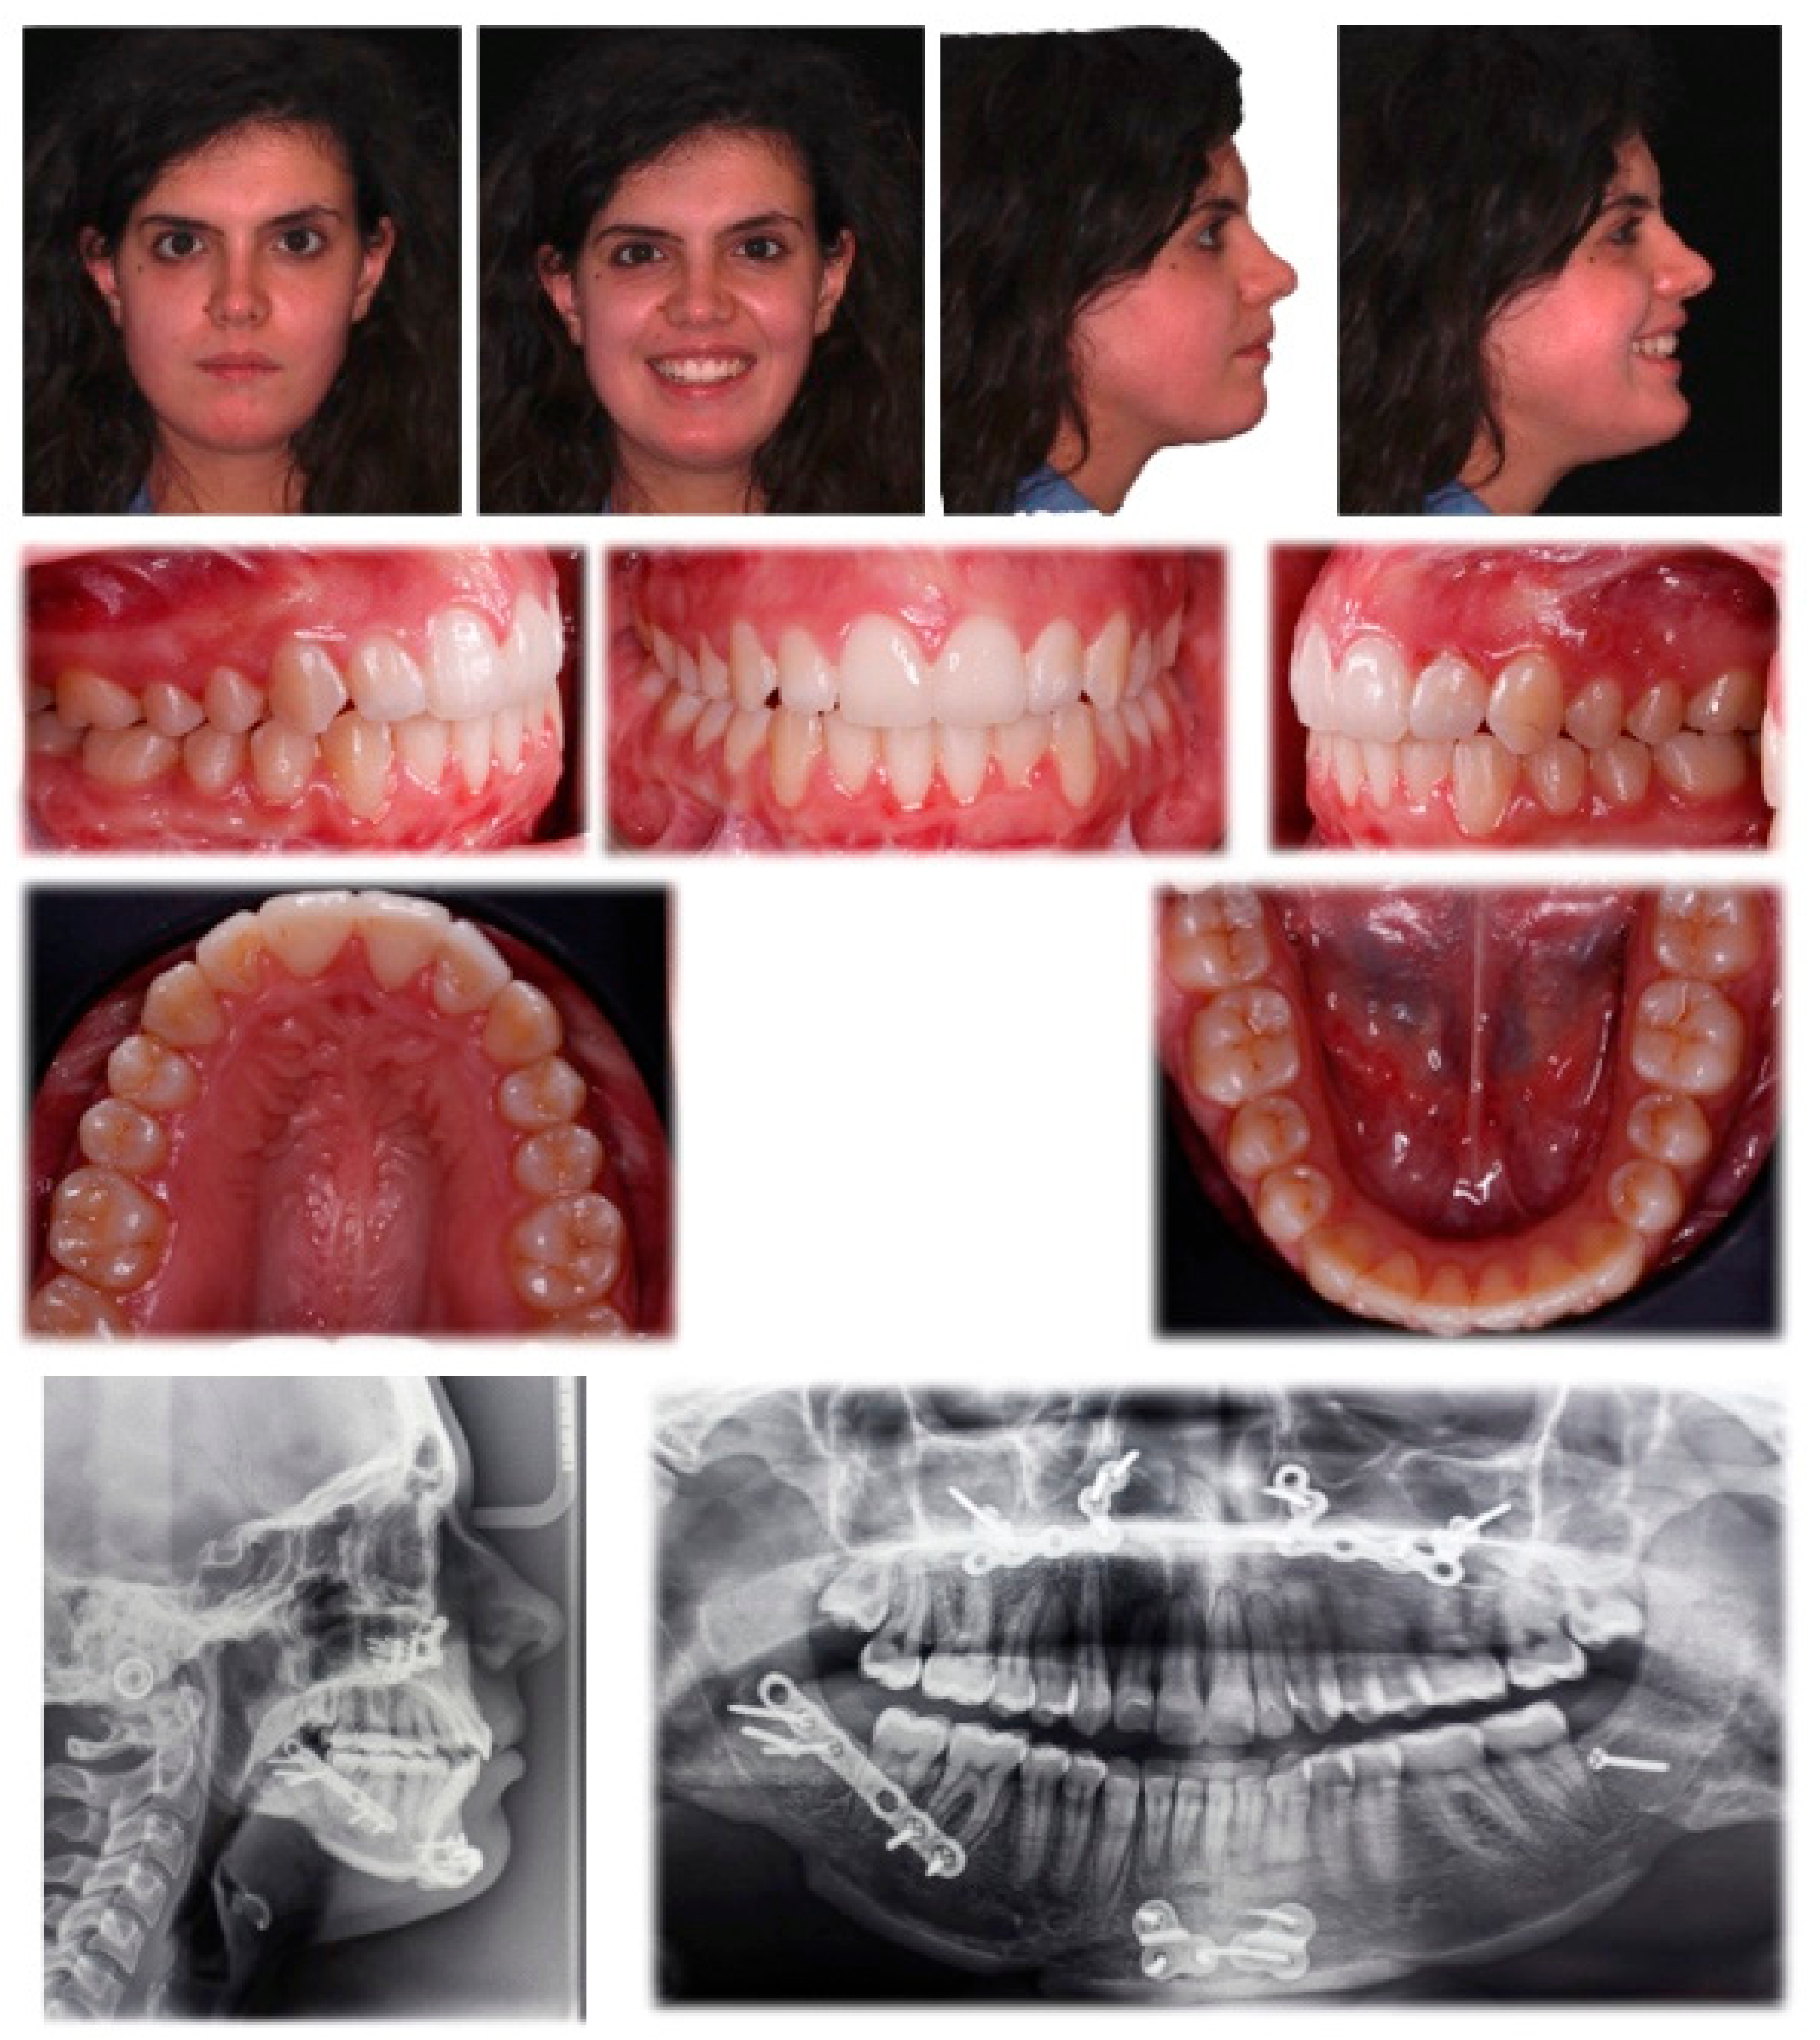

2.2. Treatment Progress

3. Results